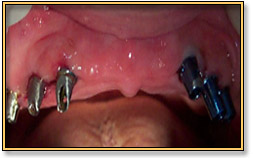

Full Mouth Replacement with Implants

This 77 year old patient was wearing upper removable dentures for the past few years. He had occasional difficulty while chewing, sneezing and coughing. The dentures used to come out and were a huge

embarrassment. Having lived a comfortable life for most of his age, it was very disheartening for him.

The first photograph shows the preoperative condition of the mouth. The second picture shows the abutments in place after the second stage surgery. The last picture is after the upper arch was completed with Metal Ceramic Bridges.